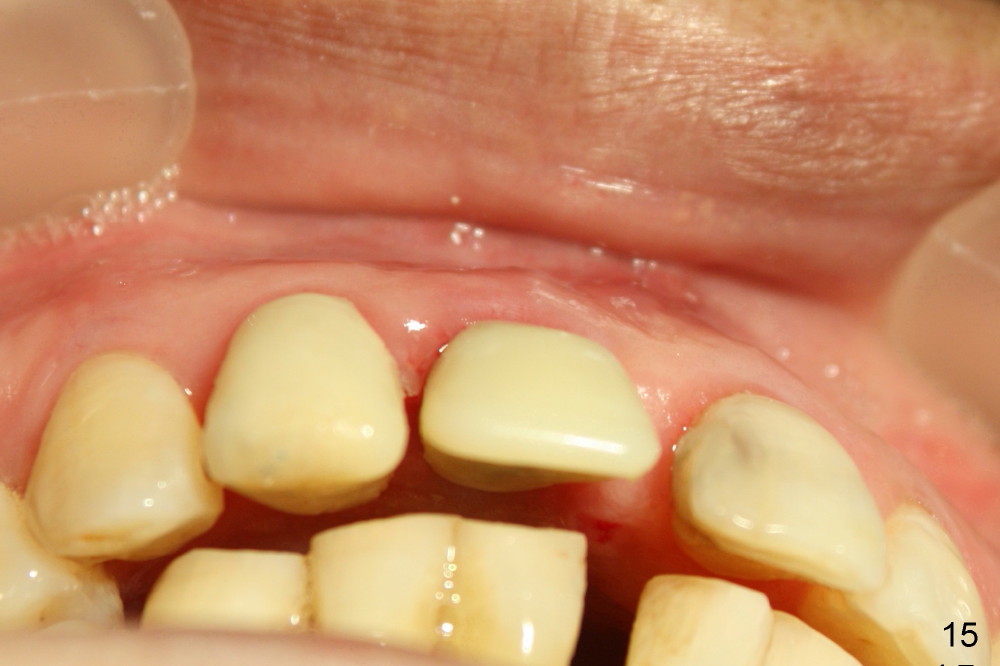

The patient returns for follow up 8 days postop and the labial margin of the provisional looks long. The metal crown is changed to a provisional at the visit. Eight days later, the provisional at the site of #8 is removed for labial margin trimming; the labial gingiva heals (Fig.14 *). The labial plate remains slightly convex (Fig.15). The labial margin of the provisional at the site of #8 is at the same level of that of #9.

Four-month follow up shows that bone graft from the tuberosity appears to have healed with the implant microthreads (Fig.17 *); there is a diastema between #8 and 9 (arrowheads). Before removal of the provisionals of #7 and 8 for final impression, new composite is added to the mesial surface of #9 as the first step of closure of the diastema (Fig.18 <).